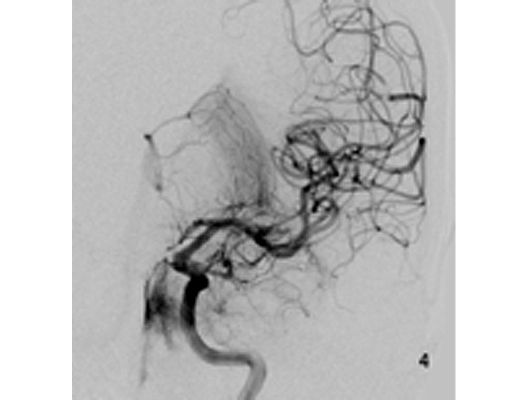

Angiographie: Rekanalisierende Verfahren

Rekanalisierende Verfahren (Wiedereröffnung von Blutgefäßen)

Mit den modernen Verfahren zur Wiedereröffnung von verschlossenen Blutgefäßen können wir Patienten mit Schlaganfall in vielen Fällen helfen. Das folgende Beispiel zeigt die angiographischen Bilder eines Patienten, der mit vollständiger Lähmung der rechten Körperhälfte und einer schweren Sprachstörung eingeliefert wurde. Ursächlich zeigte sich ein Verschluss der linken Halsschlagader, vermutlich auf dem Boden einer arteriosklerotischen Einengung (Bild 1). Das Gefäß wurde daraufhin mit einem Stent wiedereröffnet (Bild 2). Zusätzlich zeigte sich ein Verschluss der Endstrecke des Gefäßes durch Blutgerinnsel (Bild 3). Diese konnten vollständig entfernt werden (Bild 4). Der Patient erholte sich nach der Behandlung innerhalb weniger Tage vollständig.